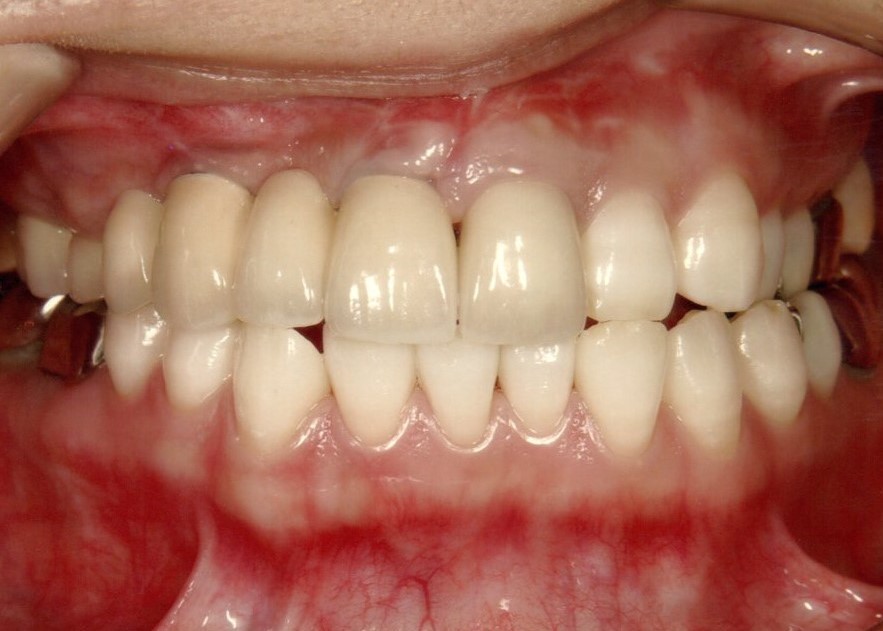

前歯インプラント

最終的な被せ物を装着すると、隣の天然歯と見分けがつかない綺麗な仕上がりになりました。